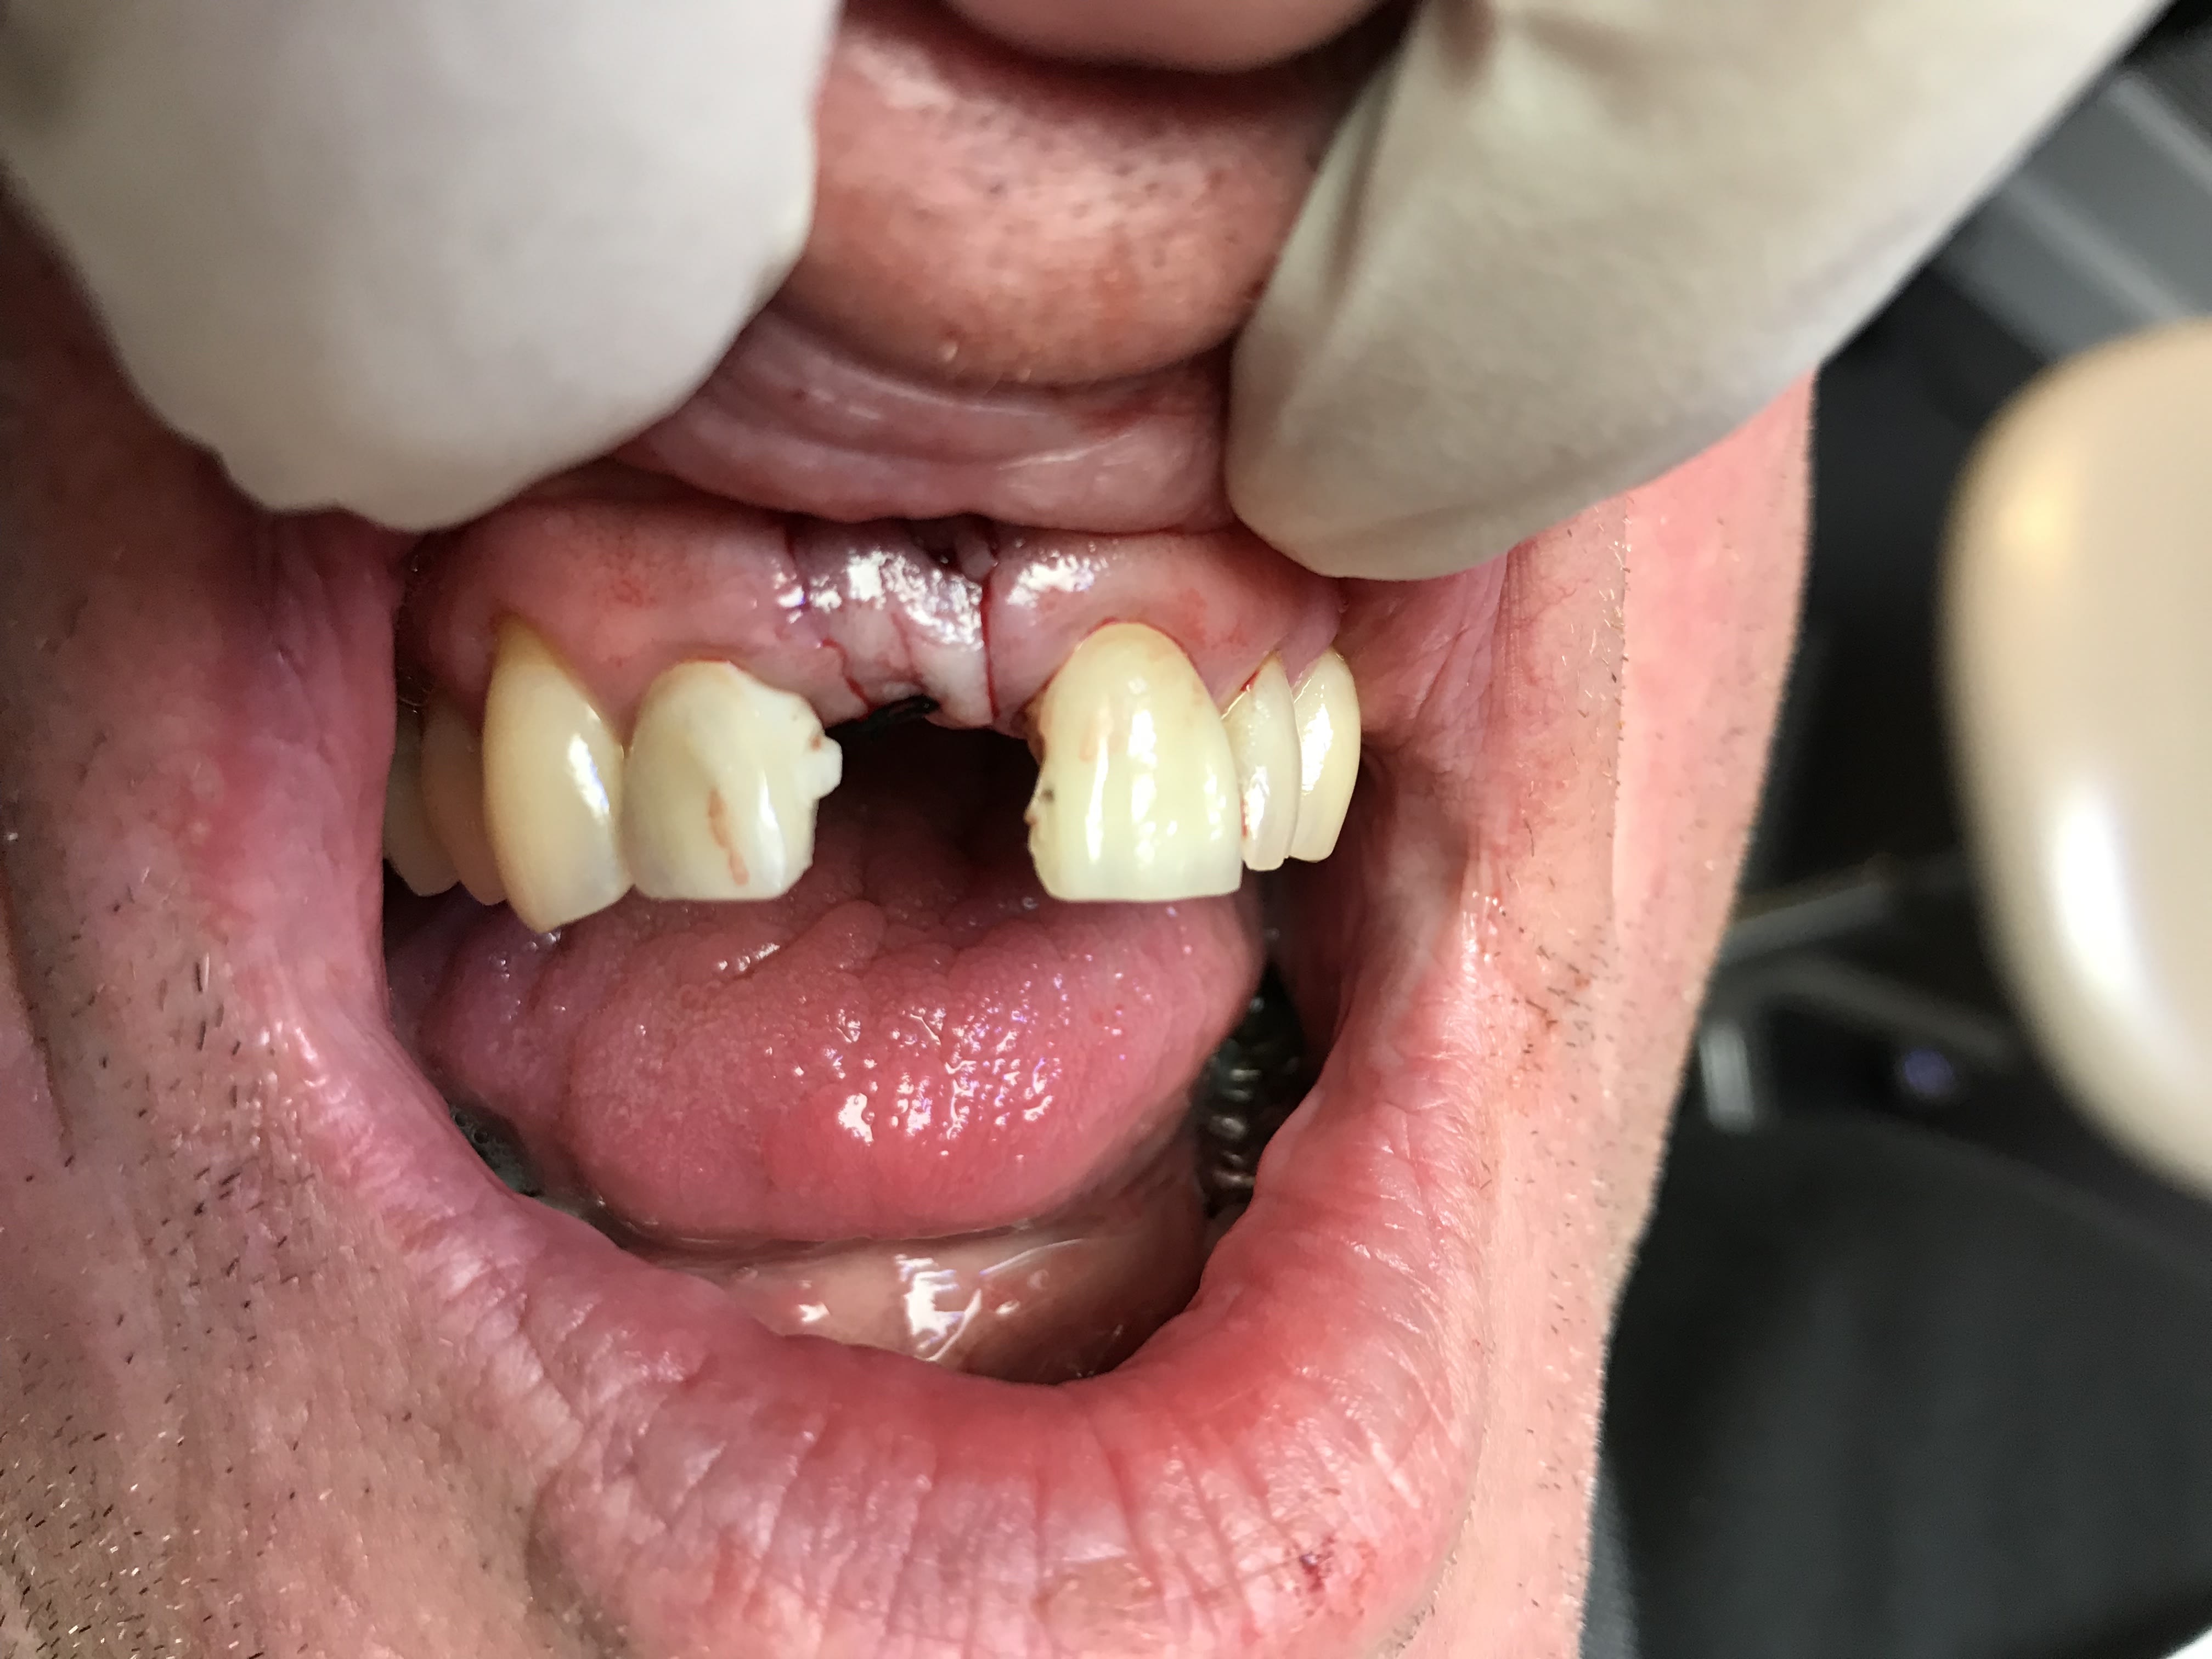

Hey ben bravo la compagnie ! C’est du propre !^^ Regardez moi voir vos bridges emax bande de vieilles branches -> ça n’a pas l’air d’être très solide.... du coup Implant plus prothèse provisoire

Et j’ai regardé les jonctions entre les piliers et l’inter , ça n’etait pas mal fait... le dentiste et le prothésiste qui avaient fait ça, avaient respecté l’ épaisseur nécessaire. Autrement dit ça m’a l’ air très fragile ce genre de bridge

Un truc que j'ai remarqué, tu as plus de casse et descellement quand les 2 racines ont des valeurs mécaniques très différentes (je pense au "débattement") et là tu avais une centrale et une latérale. Les racine n'apportent pas le même soutien, ce qui doit créer des contraintes dans l'infra-structure et le matériau d'assemblage.

A la limite, quitte à faire un bridge, j'aurais rajouté la canine.